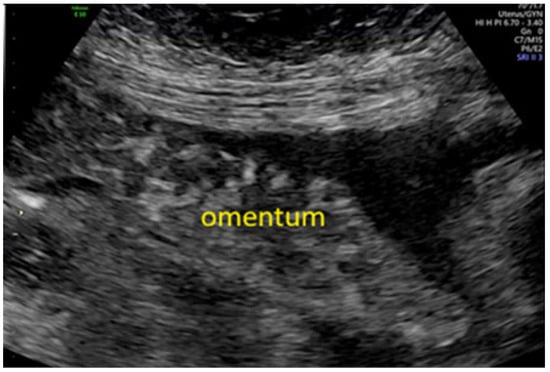

- Testa, A.C.; Ludovisi, M.; Savelli, L.; Fruscella, E.; Ghi, T.; Fagotti, A.; Scambia, G.; Ferrandina, G. Ultrasound and color power Doppler in the detection of metastatic omentum: A prospective study. Ultrasound Obstet. Gynecol. 2005, 27, 65–70. [Google Scholar] [CrossRef]

- Testa, A.C.; Ludovisi, M.; Mascilini, F.; Di Legge, A.; Malaggese, M.; Fagotti, A.; Fanfani, F.; Salerno, M.G.; Ercoli, A.; Scambia, G.; et al. Ultrasound evaluation of intra-abdominal sites of disease to predict likelihood of suboptimal cytoreduction in advanced ovarian cancer: A prospective study. Ultrasound Obstet. Gynecol. 2012, 39, 99–105. [Google Scholar] [CrossRef]

- Fischerova, D.; Zikan, M.; Semeradova, I.; Slama, J.; Kocian, R.; Dundr, P.; Nemejcova, K.; Burgetova, A.; Dusek, L.; Cibula, D. Ultrasound in preoperative assessment of pelvic and abdominal spread in patients with ovarian cancer: A prospective study. Ultrasound Obstet. Gynecol. 2017, 49, 263–274. [Google Scholar] [CrossRef]